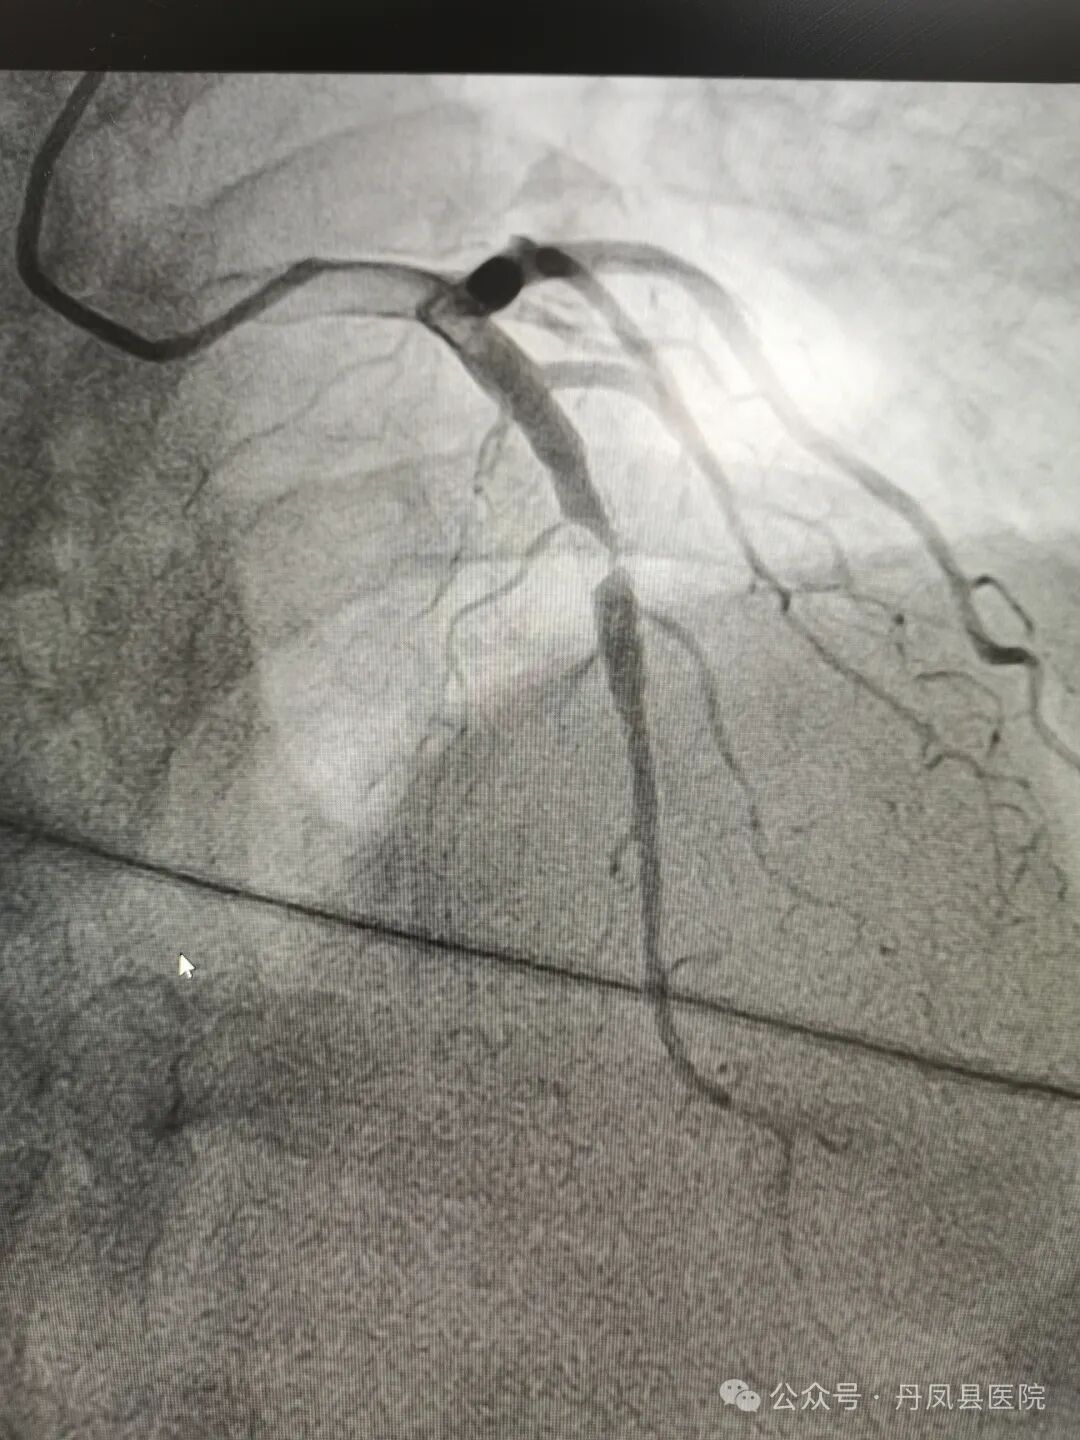

图1、图2为造影下发现病变,图3为术中球囊释放,图4为球囊释放后。